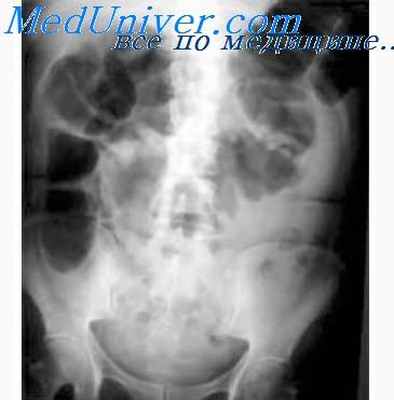

Туберкулез кишечника обнаруживают у 60–90% лиц, умерших от туберкулеза. Туберкулезные микобактерии попадают в кишечник чаще всего гематогенным или лимфоген-ным путем либо при заглатывании инфицированной мокроты, слюны и слизи, особенно при туберкулезном поражении гортани и глотки. Чаще всего поражаются дистальные отделы подвздошной и слепой кишки, аппендикс, реже- восходящая, поперечная, ободочная кишка.

Симптомы, течение. Вначале туберкулезное поражение кишечника может протекать бессимптомно или с общими симптомами — нарушением аппетита, тошнотой и тяжестью в животе после еды, слабостью, недомоганием, субфебрильной лихорадкой, повышенной потливостью, вздутием кишечника. Неустойчивым стулом, малохарактерными болями в животе. В дальнейшем боль становится более постоянной, локализуется чаще в правой подвздошной области и около пупка, при пальпации определяются плотные болезненные утолщения стенок слепой кишки и конечной части подвздошной кишки. При поражении прямой кишки наблюдаются тенезмы и ложные позывы. При туберкулезном мезадените боль локализуется в глубине живота несколько влево и книзу от пупка или по ходу брыжейки тонкой кишки. Во время рентгенологического исследования кишечника обнаруживают изъязвления слизистой оболочки, дискинетические явления, рубцовые стенозы, иногда дефекты наполнения слепой кишки. Поражение толстой кишки может быть уточнено при колоноскопии. При исследовании кала отмечают положительные реакции на скрытую кровь и пробу ребунале на растворимый белок. В крови — гипохромная анемия, лейкопения с относительным лимфоцитозом, при обострении — нейтрофильный лейкоцитоз, увеличение СОЭ.

Наиболее достоверными рентгенологическими признаками поражения стенки кишки туберкулезным процессом являются анатомические нарушения. Длительная задержка бария в петлях подвздошного отдела тонкой кишки (от 12 до 24 ч) свидетельствует о наличии анатомических нарушений данного отдела или отека складок слизистой оболочки последней петли. Единичные или множественные округлые полипоподобные образования в последней петле подвздошной кишки возникают вследствие гиперплазии лимфоидного аппарата (который в норме рентгенологически не различим, так как его диаметр равен таковому просяного зерна). Эти изменения характерны для начальной стадии ТБ кишки. Выходя на контур кишки, они формируют неровный мелко- или крупнозубчатый край пораженного отдела. В результате распада гиперплазированного фолликула образуется язвенный дефект, расположенный поперечно в стенке кишки, что рентгенологически проявляется симптомом «ниши» («рельеф ниши»), то есть стойким депо контрастного вещества, или «нишей», выходящей на контур. Наряду с вышеописанными изменениями определяются расширение или сужение просвета последней петли подвздошной кишки, ригидность стенок, отсутствие перистальтики, обрывистость, грубость, отечность складок слизистой оболочки.